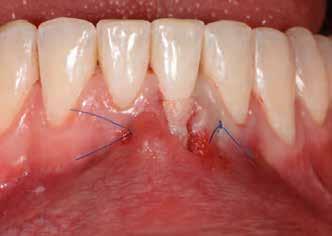

A foggyökér óvatos, atraumatikus eltávolítását követően excochleáltuk a parodontális és periapikális gyulladásos folyamatok eredményeként jelen lévő sarjszövetet. Az alapos tisztítás és a bukkális csontfal hiánya miatt indokolt membrántechnika megfelelő kivitelezése céljából mukoperioszteális lebenyt képeztünk, a lebeny tervezésénél arra törekedtünk, hogy az a lehető legkisebb méretű legyen és a második kisőrlő fog helyén lévő implantátum hámtapadását ne érintse, illetve, hogy lehetővé tegye a szemfog parodontális kezelését is (3., 4. ábra). Az alveoláris csont megőrzésének és regenerációjának segítése céljából a fog eltávolításával egy időben alveólus prezervációt végeztünk Stikcy Bone™ és PRF membránok segítségével, melyek előállításánál követtük a J. Choukroun által megadott vérvételi és centrifugálási protokollt (20). Kizárólag Process for PRF Duo Quattro System eszközöket, centrifugát, vérvételi egységet és csöveket, a membránok előállításához PRF Box-ot használtunk. Az A-PRF és S-PRF csöveket a PomPac eljárásnak megfelelően 4 °C-ra előhűtöttük. A Stikcy Bone™ készítmény előállításához Purgo™ xenografot használtunk. Az alveolust a grafttal feltöltöttük, tömörítő műszerrel enyhe kompreszsziót, illetve vertikális irányban 10 százaléknyi túlkompen-

zációt alkalmaztunk (5., 6. ábra). Ezt követően a palatinális marginális gingivát óvatosan alápreparálva a bukkális defektust, valamint az okkluzális felszínt keresztirányban A-PRF membránokkal borítottuk (7. ábra). A mukogingivális lebenyt – annak megnyújtása nélkül – a helyére fektettük és varratokkal rögzítettük, per primam sebzárást nem végeztünk (8., 9. ábra). A varratokat 2 hét után távolítottuk el, a varratszedésig a sebgyógyulás támogatására per os 1000 mg/nap C- és 12 000 NE/nap D-vitamint adtunk (20). A műtéti beavatkozást 24 hét gyógyulási időszak követte, melynek során sem helyi, sem gyógyszeres kezelés nem történt, az esztétikum javítása érdekében a páciens ideiglenes kivehető fogpótlást használt. A csontos gyógyulás ellenőrzése és az implantáció tervezése céljából állcsonti CT felvételt készítettünk, illetve lenyomatvételt végeztünk. A CT felvételen tökéletes csontos gyógyulást észleltünk, az alveolaris csont volumene teljes mértékben megtartott volt (10. ábra), a klinikai kép is ennek megfelelően alakult (11., 12. ábra) A Trishape Implant Studio™ a korábbi csont augmentáció területén, a felső állcsontnál áltagosnak számító D2-D3 csontminőséget jelzett (13. ábra). A lenyomat alapján készített gipszmodellt szkennelve virtuális mintát nyertünk. A CBCT felvétel és a virtuális modell adatait a Dual Scan protokoll (21) elveinek megfelelően használtuk fel az implantációs sablon (New Age Dental Kft, Nemeskéry Károly) készítéséhez (14., 15., 16. ábra). Az implantátum (Ankylos C/X A11) behelyezése teljesen navigált módon, 35 Ncm primer stabilitással történt (17., 18. ábra). Az implantátumra a fogtechnikus (D1 Dental Kft., Garamvári Csaba) által előzetesen elkészített csavarozott, ideiglenes fogpótlást rögzítettünk a gyártó által előírt 15 Ncm-es nyomatékkal, az ideiglenes korona az okklúzióban és artikulációban nem vett részt (19., 20., 21. ábra). A front- és prémoláris régióban, amennyiben lehetséges, mindig nyílt gyógyulási protokollt választunk, azonnali ideiglenes restaurátumot készítve, így biztosítva elegendő időt a lágyrészek maturációjához (23, 24, 25, 26, 27). A kontrollvizsgálatok során havonta ellenőriztük az ideiglenes fogpótlás és az implantátum stabilitását, valamint a lágyrészek állapotát, korrekciós beavatkozás vagy az ideiglenes korona emergencia-profiljának változtatása nem volt szükséges (22. ábra). Két hónapos terhelésmentes időszakot követően, csont-tréninget alkalmaztunk részleges terheléssel, a teljes terhelést a hatodik hónap végére értük el, és megkezdtük a definitív protetikai ellátást. Az ideiglenes restaurátum eltávolításakor az alveoláris struktúrák tökéletes gyógyulását észleltük, a páciens ínye békés, reakciómentes volt, megfelelő mennyiségű keratinizált, feszes ínnyel rendelkezett (23. ábra). Az implantátum stabilitása Periotest-tel -8 értékű volt. Cerec Omnicam rendszerrel digitális lenyomatot vettünk (24. ábra), és a fogtechnikus (Prodont Silver Kft., Panyi János) által ragasztott, csavarozott hibridkerámia koronát készíttettünk nem indexált Ankylos C/ titanium-base fej felhasználásával, amelyet az előírás szerinti 15 Ncm-es nyomatékkal rögzítettünk (25., 26 ábra), majd ellenőriztük az okklúziót és az artikulációt (27. ábra). A beavatkozást követően 6 hónappal az alveoláris struktúrák stabilak, a röntgenfelvételen a csontállomány megtartott, a beteg panaszmentes, rágó funkciója kifogástalan, az esztétikai eredménnyel teljes mértékben elégedett (28., 29., 30. ábra)